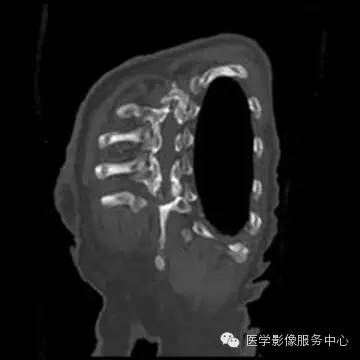

胸部CT平扫显像能力优于X线平片,显示UAPA典型征象更明显,偶尔可见患侧肺动脉段缺如。当见患侧失去正常肺小叶结构时,提示原发病导致肺泡发育障碍;另外可见肺纹理纤细走行僵直、肺门菲薄,可伴发肺大泡、间质改变及其他肺部病变。